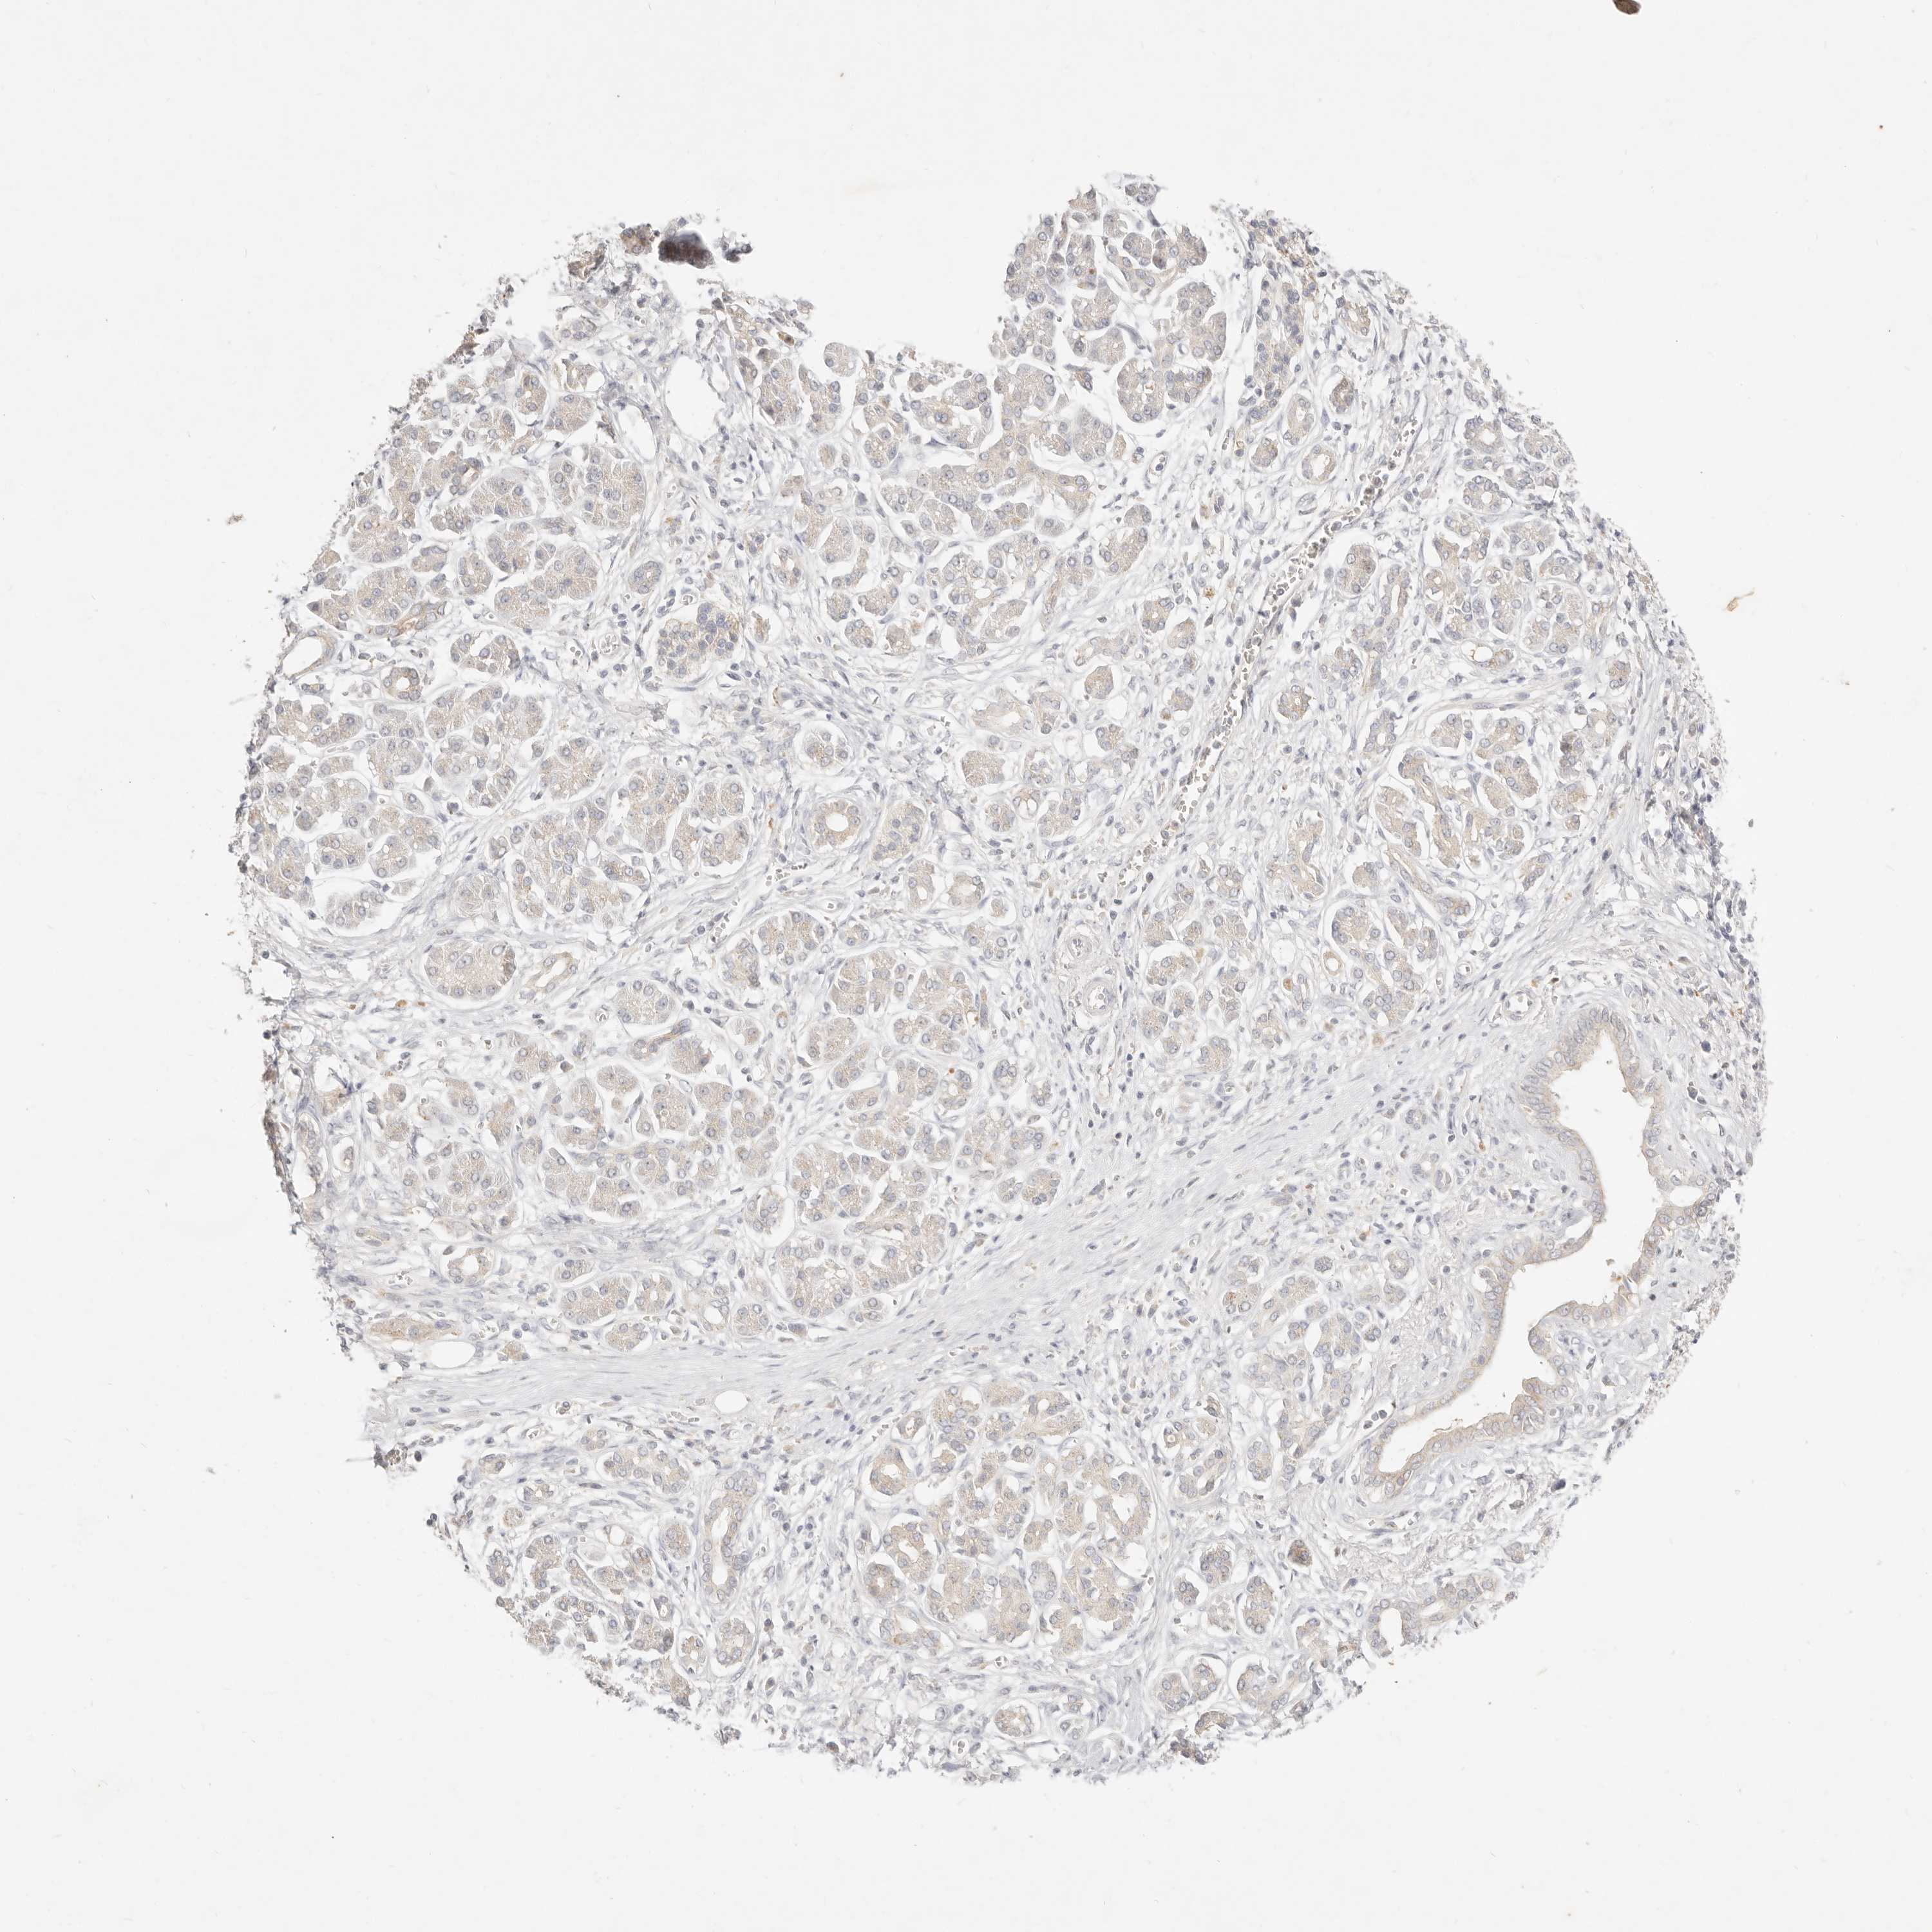

PANCREATIC CANCER - Protein expressioni

A mouse-over function shows sample information and annotation data. Click on an image to view it in a full screen mode. Samples can be filtered based on level of antibody staining by selecting one or several of the following categories: high, medium, low and not detected. The assay and annotation is described here.

Note that samples used for immunohistochemistry by the Human Protein Atlas do not correspond to samples in the TCGA dataset.

Antibody stainingi

Antibody staining in the annotated cell types in the current human tissue is reported as not detected, low, medium, or high, based on conventional immunohistochemistry profiling in selected tissues. This score is based on the combination of the staining intensity and fraction of stained cells.

Each image is clickable and will lead to virtual microscopy that enables deeper exploration of all samples and also displays staining intensity scores, fraction scores and subcellular localization as well as patient and tissue information for each sample.

Antibody HPA021192

Antibody HPA021195

Antibody HPA028759

Antibody CAB021094

Staining

High

Medium

Low

Not detected

Intensity

Strong

Moderate

Weak

Negative

Quantity

>75%

75%-25%

<25%

None

Location

Nuclear

Cytoplasmic/membranous

Cytoplasmic/membranous,nuclear

Adenocarcinoma, NOS

Adenocarcinoma, metastatic, NOS